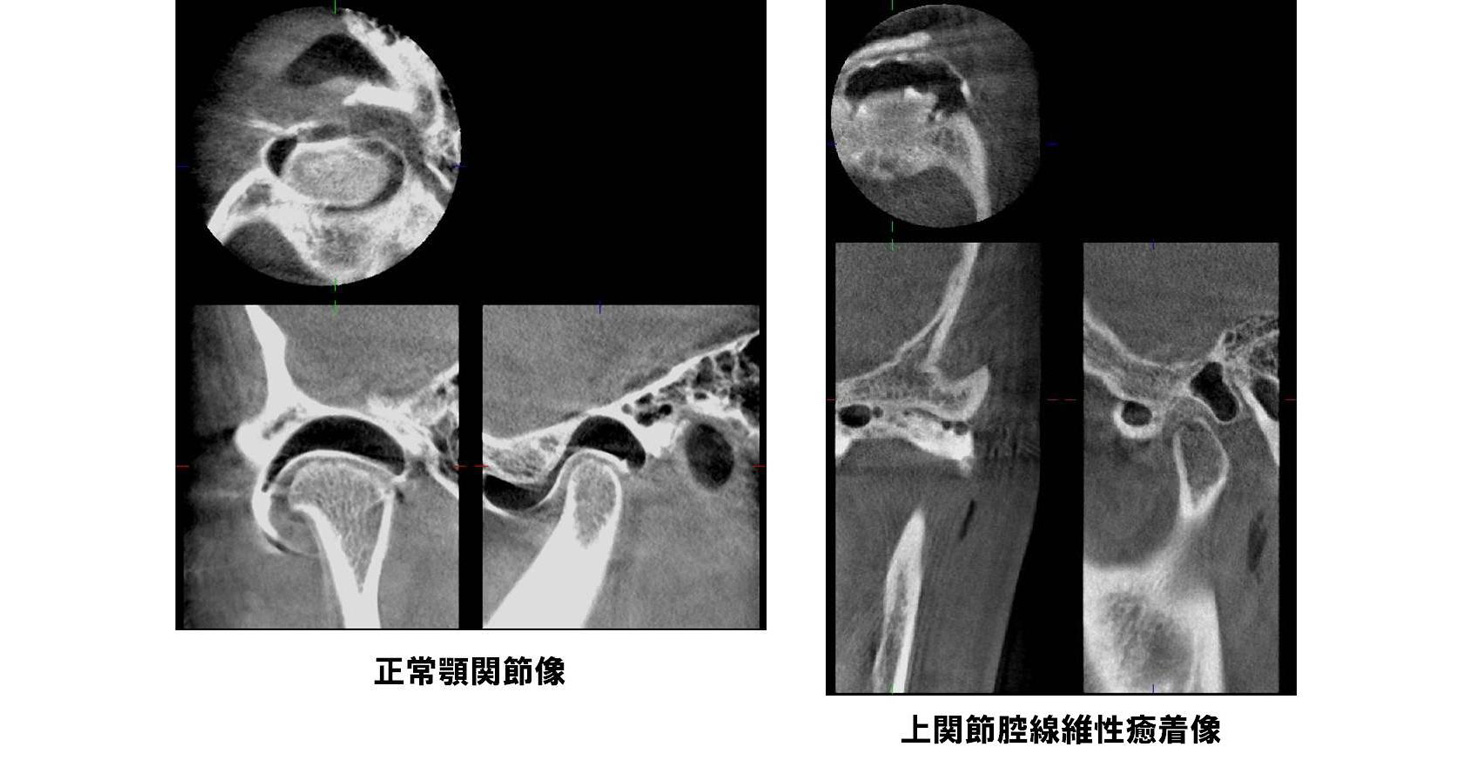

機能障害 顎関節症(注2)(注3)、顎関節強直症、顎変形症など(注2)[顎関節症]

顎関節症とは口を開けると顎の関節にカクカク音がする、顎の関節が痛い、口が開かない、顎がだるい、肩こりや頭痛がする、といった症状があり、関節雑音、開口障害、咀嚼障害を呈する疾患です。

顎関節症は正しく診断・治療すればそのほとんどが軽快しますが放置しておくと経時的に変形性関節症にまで悪化することが知られています。

当科では顎関節造影検査、関節腔内洗浄療法、スプリント療法(いずれも予約制)などの顎関節症専門外来を行っております。

(注2)[顎関節症]

当科では2008年3月よりベラビューエポックスを導入しました。この装置はパノラマ画像と3次元的歯科用CT画像が低照射量、短時間で撮影できます。歯の根尖病巣や顎骨病変、顎関節造影検査での診断やインプラント、抜歯などの術前精査において有効に用いられています。